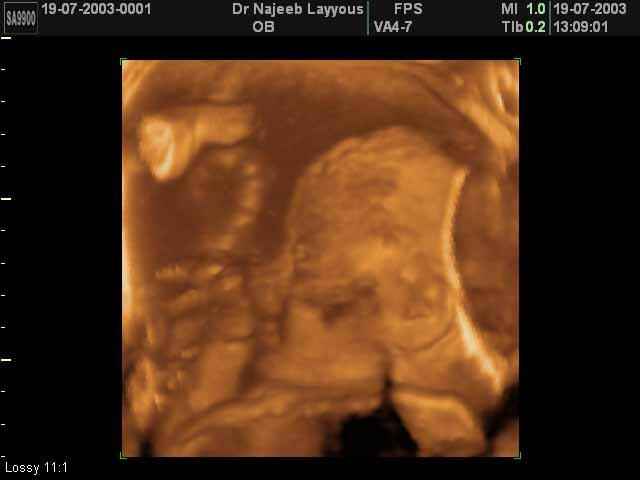

- صور لوجه الجنين في داخل الرحم

- صور جانبية لرأس الجنين

صور جانبية لرأس الجنين بجهاز الالتراساوند ثلاثي الأبعاد | الدكتور نجيب ليوس